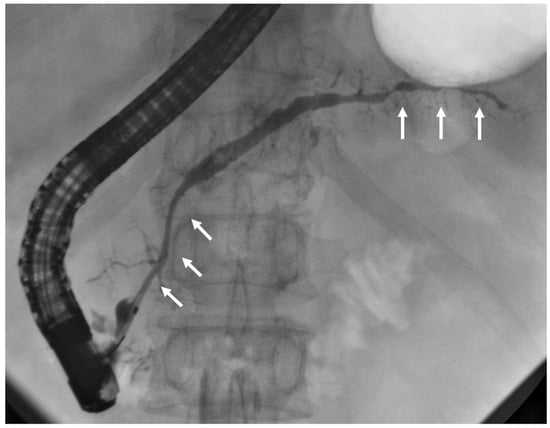

EUS is useful for evaluating IgG4-related cholecystitis, which can present in diffuse or localized forms. Imaging features include continuity of the mucosal layer, a smooth luminal surface, and preservation of wall stratification. Localized IgG4-related cholecystitis may appear similar to subepithelial lesions (Figure 7), helping distinguish it from GB cancer. In some cases, cystic lesions within the GB wall, resembling ADM, have been reported in localized disease [85].

Figure 7.

Endoscopic ultrasonographic findings showing a localized thickening of the gallbladder wall at the fundus, with the lesion located within the submucosal layer in localized IgG4-related cholecystitis (arrows).